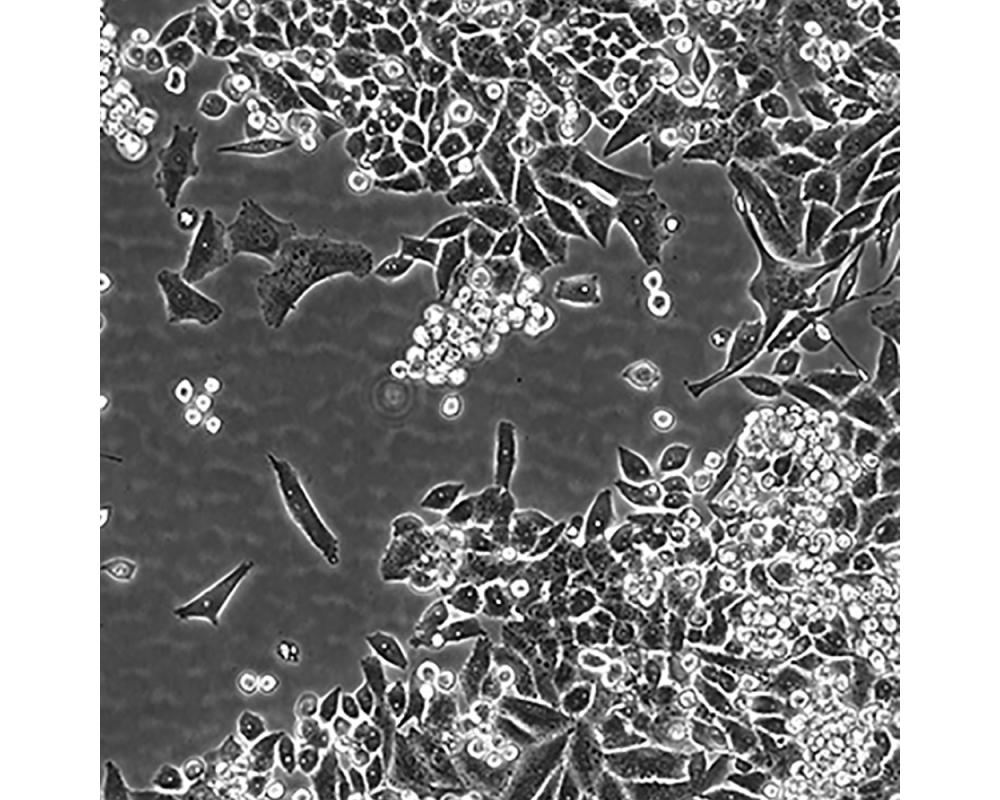

MiaPaCa-2

中文名稱 人胰腺癌細胞

組織來源 胰腺導管癌;男性

生長特性 貼壁

培養基 1640,90%;FBS,10%;雙抗。

傳代方法 1:2-1:4

培養條件 Atmosphere: Air, 95%; CO2, 5%。Temperature: 37℃